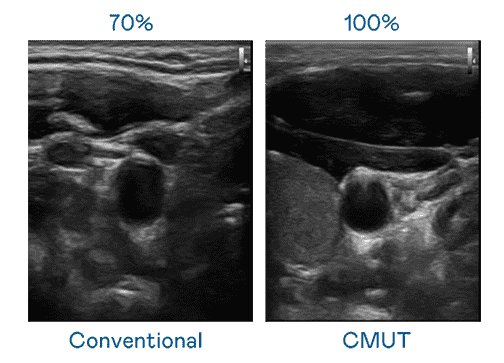

CMUT 技术是一种用电容式微机电元件来产生超音波讯号的技术。。。与传统 PZT 压电式技术相比,,CMUT 频宽增加 30%,,,更宽频的超音波讯号让影像解析度大幅提升,,,是实现高影像品质医疗超音波扫描、、、、促进精准医疗发展的关键技术。。。

大频宽带来超清晰影像

超音波影像的解析度高低,,,首先取决于探头能发出的讯号频宽。。赏金国际 CMUT 可提供高清晰的超音波讯号,,,提供高频宽、、、、高灵敏度、、影像纹理细节更高的超音波影像,,协助医护人员缩短影像判读时间及利用精准的医疗影像进行诊断。。